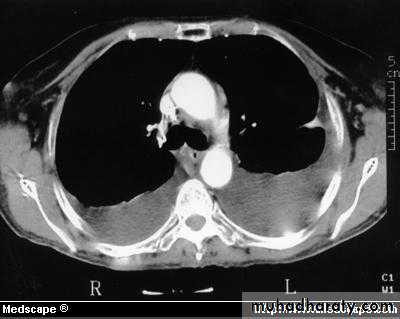

Computed tomography scan of the chest demonstrates a mass in the right upper lobe adjacent the pleura (*). Irregular soft-tissue thickening of the pleural surface (arrow) and pleural effusion (E) are present. The findings are most consistent with primary lung neoplasm with pleural metastasis and malignant pleural effusion. Results of thoracentesis were positive for malignant cells (adenocarcinoma).

Computed tomography of chest shows bilateral pleural effusions